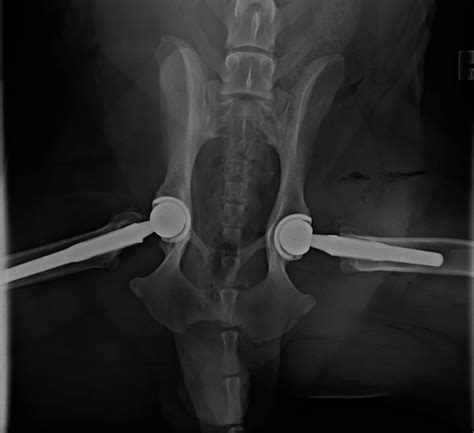

Joanne Crawford Blog